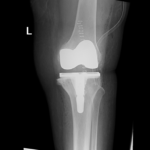

Your doctor will diagnose osteoarthritis based on the medical history, physical examination, and X-rays.

X-rays typically show a narrowing of the joint space in the arthritic knee.

The surgery is performed under spinal or general anesthesia. Your surgeon will make an incision in the skin over the affected knee to expose the knee joint. Then the damaged portions of the femur bone are cut at appropriate angles using specialized jigs. The femoral component is attached to the end of the femur with or without bone cement. The surgeon then cuts or shaves the damaged area of the tibia (shinbone) and the cartilage. This removes the deformed part of the bone and any bony growths, as well as creates a smooth surface on which the implants can be attached. Next, the tibial component is secured to the end of the bone with bone cement or screws. Your surgeon will place a plastic piece called an articular surface between the implants to provide a smooth gliding surface for movement. This plastic insert will support the body’s weight and allow the femur to move over the tibia, similar to the original meniscus cartilage. The femur and the tibia with the new components are then put together to form the new knee joint. To make sure the patella (knee cap) glides smoothly over the new artificial knee, its rear surface is also prepared to receive a plastic component. With all the new components in place, the knee joint is tested through its range of motion. The entire joint is then irrigated and cleaned with a sterile solution. The incision is carefully closed, drains are inserted and a sterile dressing is placed over the incision.